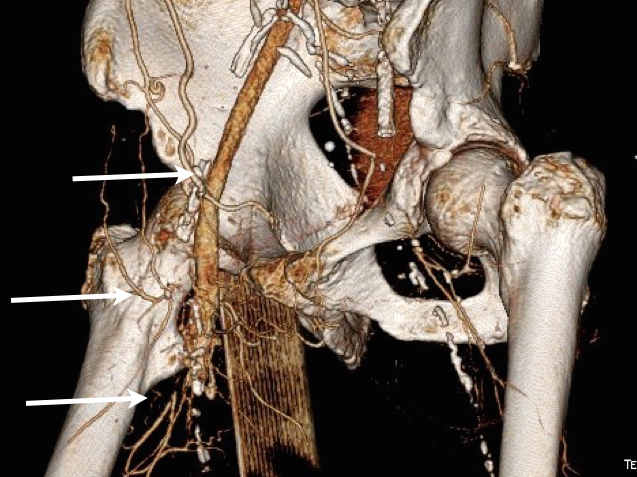

Let me show you one of the first cases I did after returning to Cleveland. I am now practicing at Fairview and Avon Hospitals, premier flagship hospitals in the Cleveland Clinic fleet, on Cleveland’s west side, and a patient arrived while I was on call with sudden onset of pain in his leg from a lack of blood flow. He had occlusive atherosclerotic plaque extending from his external iliac artery to the above knee popliteal artery causing ischemic rest pain.

I contacted LeMaitre Vascular and got in touch with your representative, L. Fisher, who promptly sent the Moll Ring Cutters I needed to perform a remote endarterectomy of the patient’s occlusive external iliac and superficial femoral artery plaque. The technical details of remote endarterectomy are have been covered in my blog (https://vascsurg.me/?s=endore), but in the end, through a 7cm incision in the groin (don’t believe the hype, this is minimally invasive), I restored his arteries to their original open condition. Shown below are the results. It was with great sadness that I heard that the LeMaitre Vascular equipment being sent were the last of the stock available in North America. The patient did very well, with the operation completed well before lunch, and is recovering rapidly from his small wound and big rescue. He gets to walk out of the hospital on two legs, but also with the surety that he avoided a major bypass operation, and avoided the short term gains of stenting from the aorta to the profunda -more peel packs and landfill items and a dubious long term durability. Hey, I even used a XenoSure patch on the common femoral.